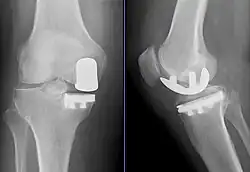

Radiographs of a knee arthroplasty of the medial compartment